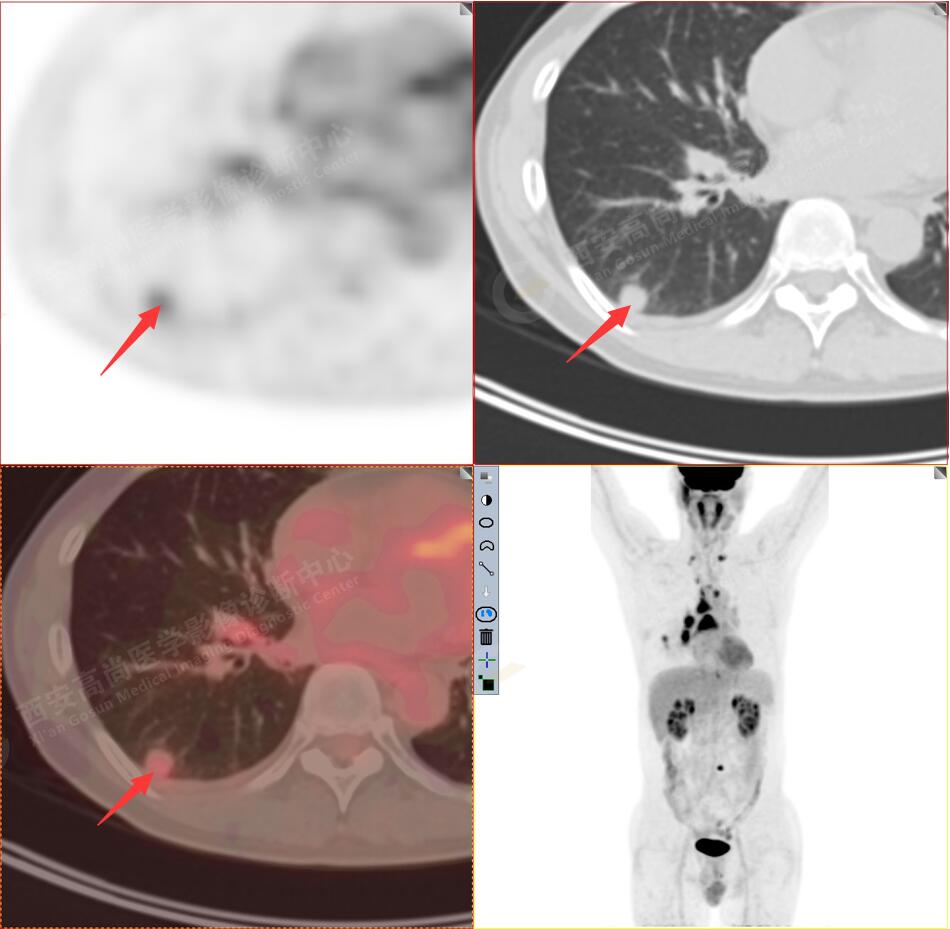

2.以下為全身多發(fā)轉移灶

2.雙肺多發(fā)高密度小結節(jié)灶(最大徑約0.7cm),部分較大結節(jié)呈FDG代謝略增高,均考慮為轉移性病變。

4.右后胸膜輕度增厚,形成多個條狀軟組織病變,呈FDG代謝輕度異常增高,考慮為轉移性病變;右側胸腔微量積液。